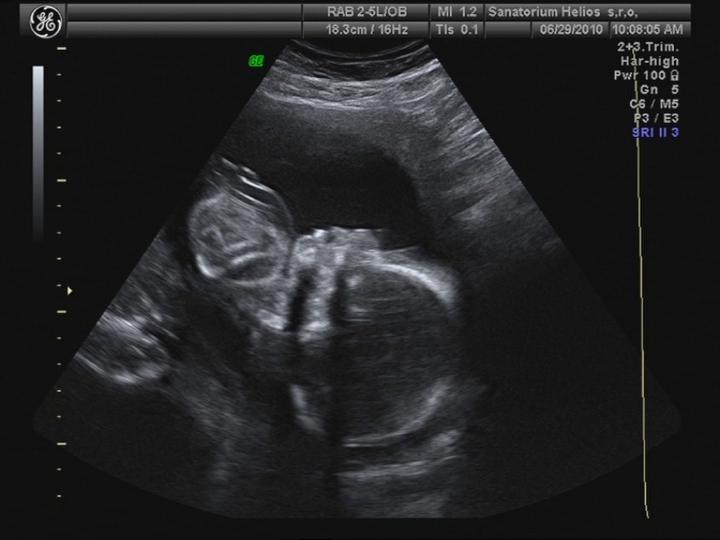

Byla jsem na UTZ, odpovídáme 10+4 tt a všechno je v pořádku... 🙂